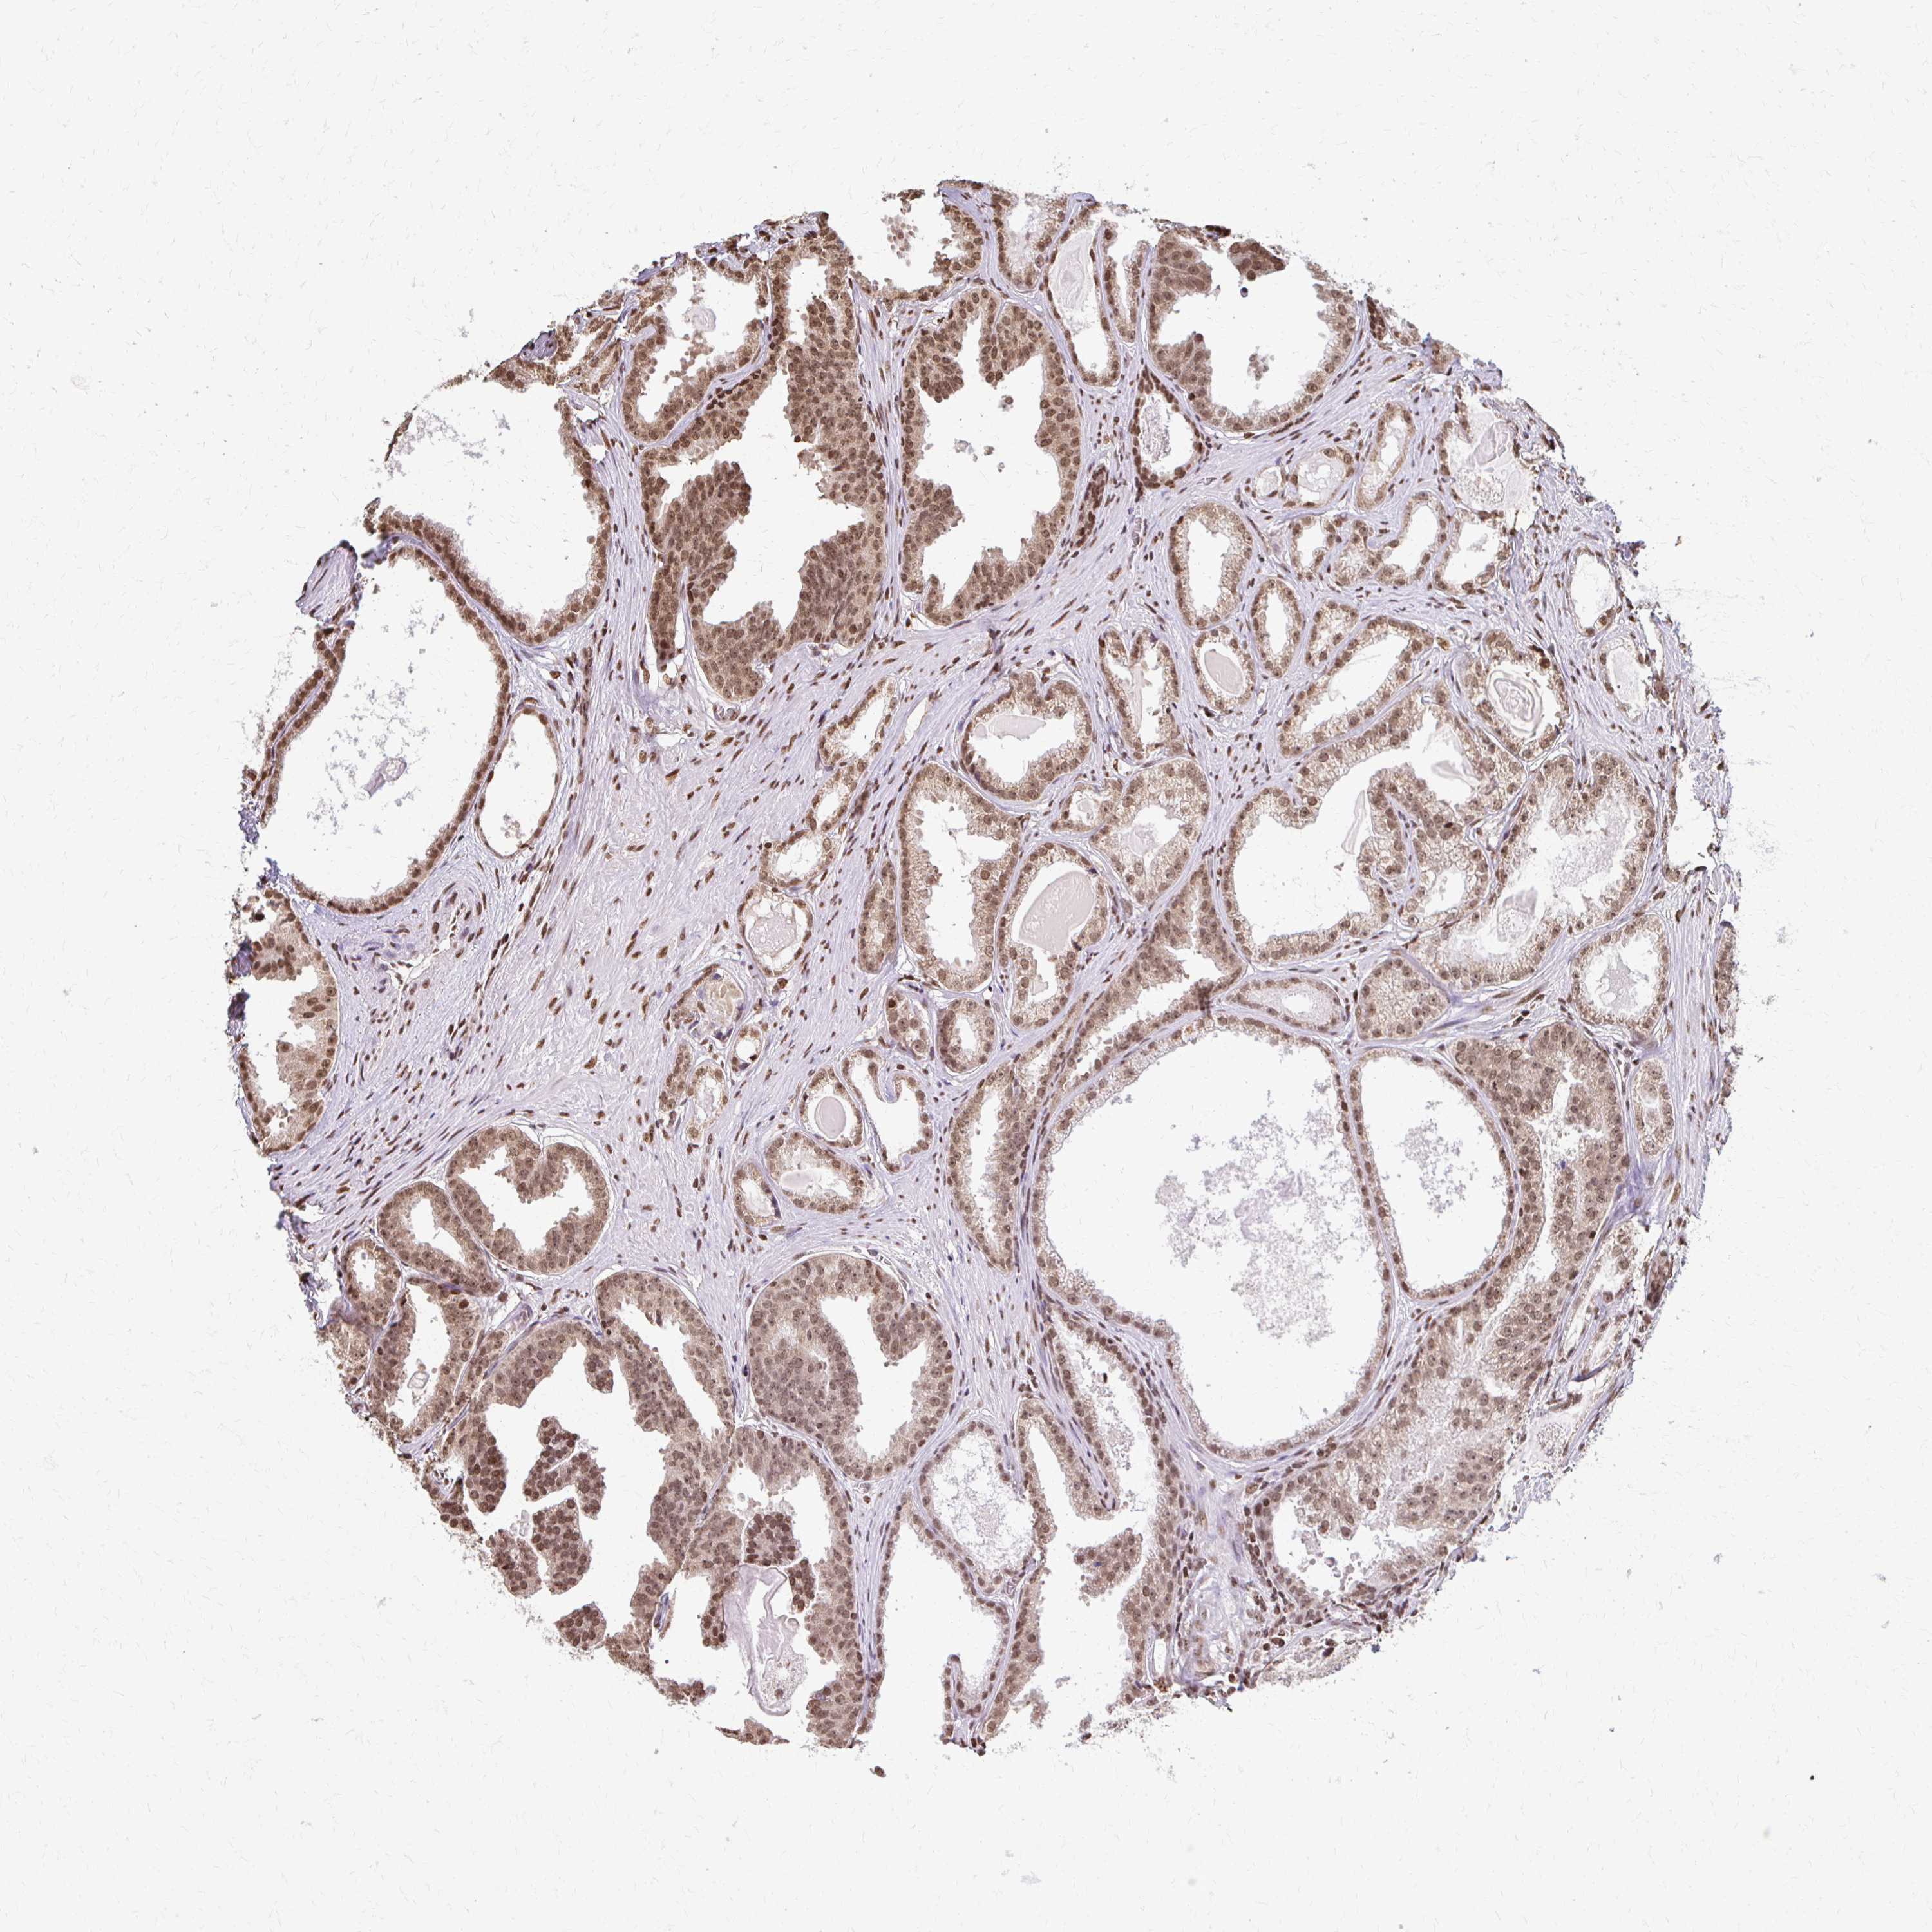

PROSTATE CANCER - Protein expressioni

A mouse-over function shows sample information and annotation data. Click on an image to view it in a full screen mode. Samples can be filtered based on level of antibody staining by selecting one or several of the following categories: high, medium, low and not detected. The assay and annotation is described here.

Note that samples used for immunohistochemistry by the Human Protein Atlas do not correspond to samples in the TCGA dataset.

Antibody stainingi

Antibody staining in the annotated cell types in the current human tissue is reported as not detected, low, medium, or high, based on conventional immunohistochemistry profiling in selected tissues. This score is based on the combination of the staining intensity and fraction of stained cells.

Each image is clickable and will lead to virtual microscopy that enables deeper exploration of all samples and also displays staining intensity scores, fraction scores and subcellular localization as well as patient and tissue information for each sample.

Antibody HPA061982

Staining

High

Medium

Low

Not detected

Intensity

Strong

Moderate

Weak

Negative

Quantity

>75%

75%-25%

<25%

None

Location

Nuclear

Cytoplasmic/membranous

Cytoplasmic/membranous,nuclear

Adenocarcinoma, High grade

Adenocarcinoma, Medium grade

Adenocarcinoma, Low grade